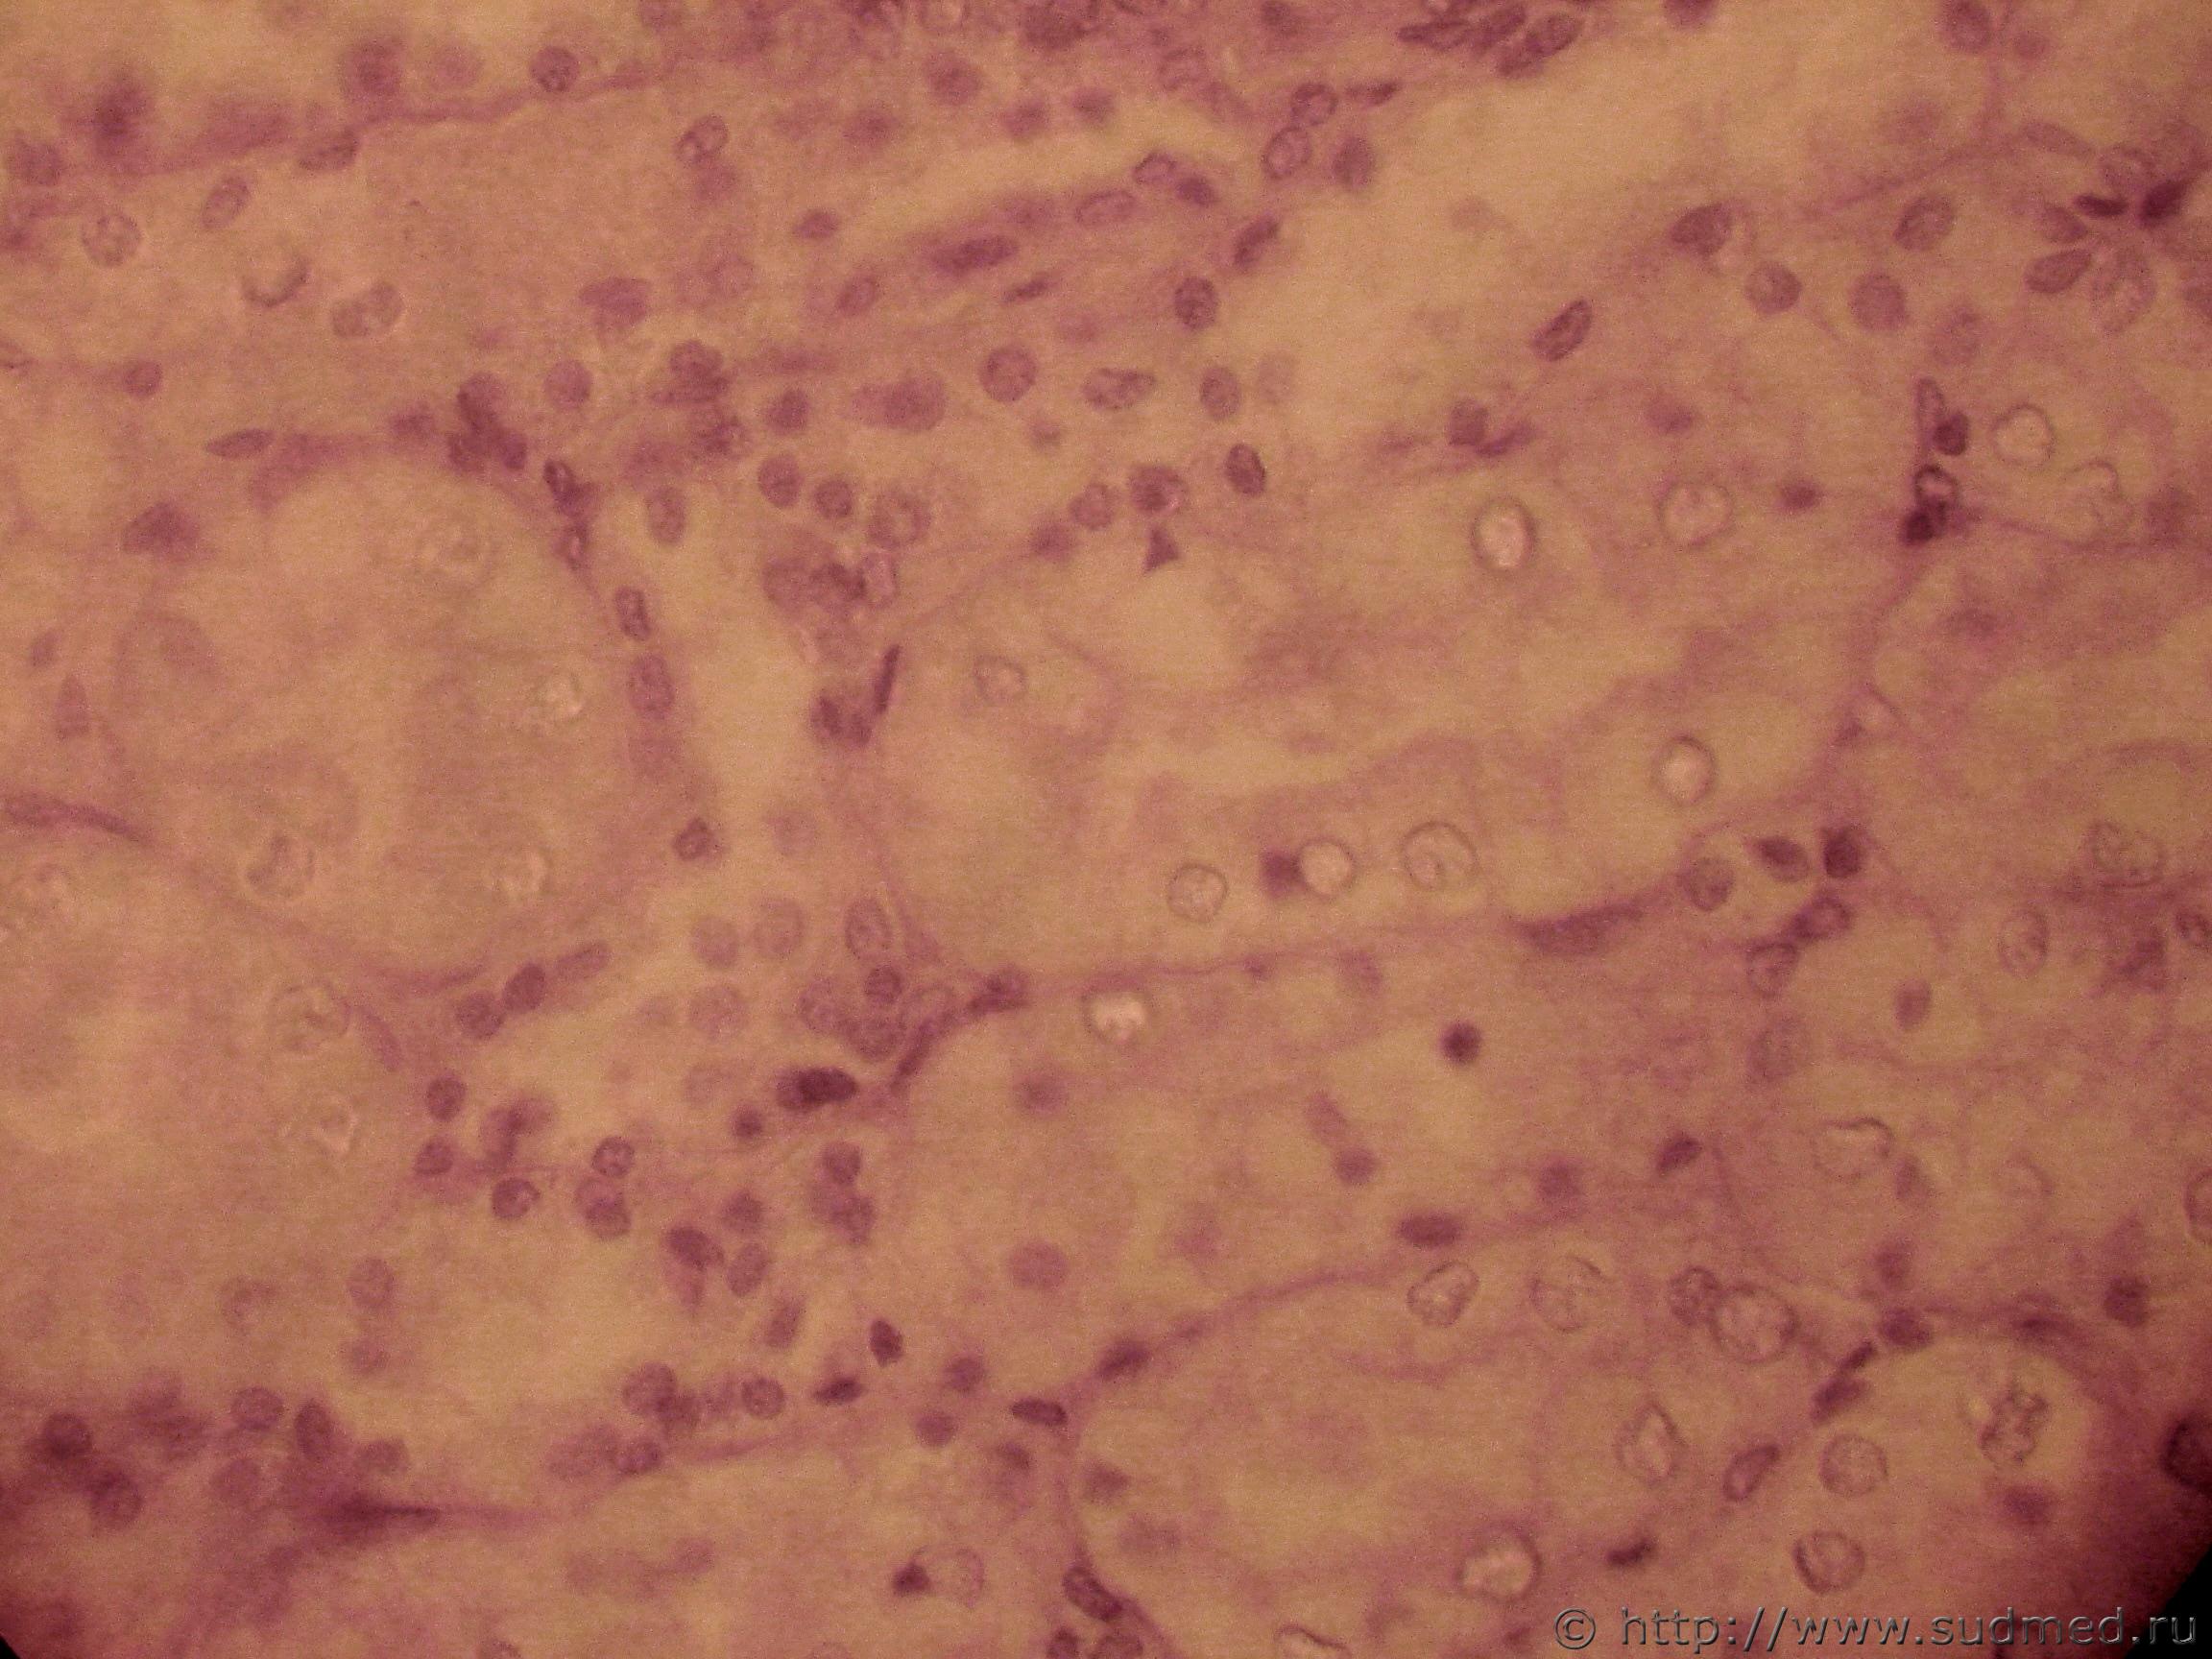

Болезнь Куру относится к прионовым заболеваниям.

В гистологических срезах отмечается вакуолизация, смерть нейронов и выраженный глиоз

Срез 1 и 2